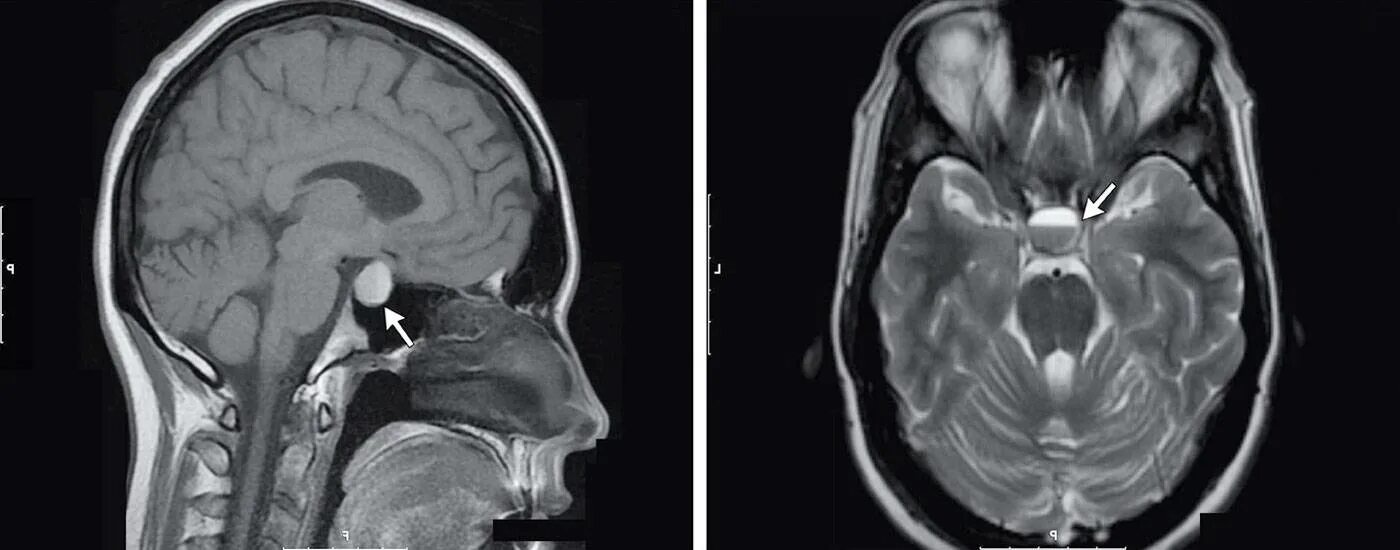

Гипофиз мрт норма